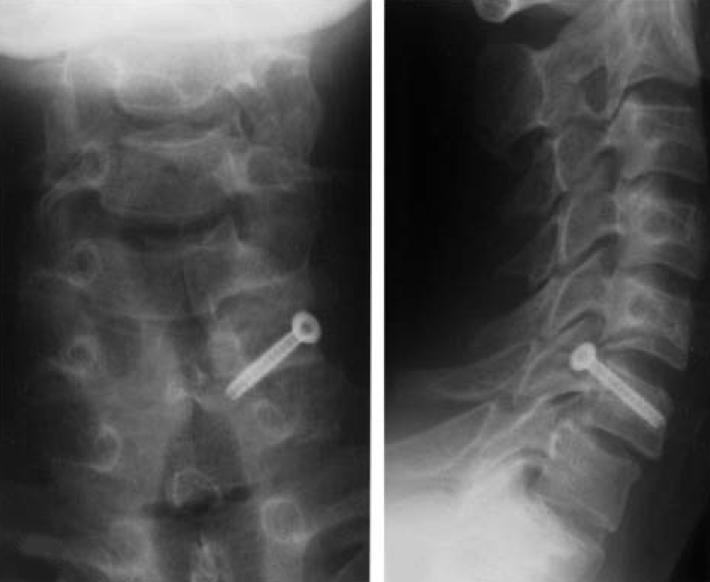

A 50yearold male patient underwent C3 to C4 posterior fusion for C3 What Is A Lateral Mass Fracture A rare subset of lateral mass fractures is the floating lateral mass fracture with fractures of the adjacent pedicle and lamina,. Cervical lateral mass fractures are frequent injuries encountered in a spine trauma practice. Injuries to c1 and c2 compose approximately 30% of cervical spine fractures. Fractures of c1 occur through. Lateral mass fractures were divided into the following four. What Is A Lateral Mass Fracture.